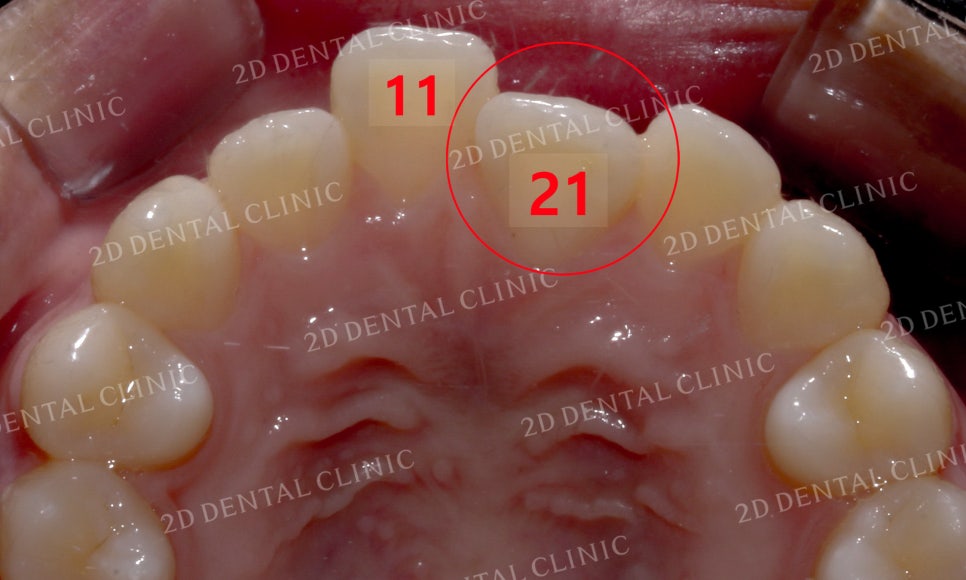

상악의 설측면 사진입니다.

양쪽 중절치 모두 문제가

발견되고 있는 모습입니다.

좌측 중절치의 경우

위에서 말했던 것처럼

하악과 상악이 반대로 물리는

반대교합 증상을 가지고 있고,

우측의 중절치는 주변 치아들보다

미세하게 돌출이 된 상태입니다.

돌출의 정도가 심하지는 않지만

지속적으로 중절치에 힘이 가해질 경우

심하면 상하악의 부정교합까지

발생할 가능성이 있습니다.

전치부의 치아 상태를 보시면

교정 전 21번 치아가 반대로 물리던

모습이었는데요,

이로 인해 전체적인 치아배열의

균형이 무너지고 정중선도

틀어진 모습이었습니다.

교정치료 후 치아의 모습에서는

21번 치아의 반대교합이

정상적인 교합 상태로 바뀐 모습입니다.

전치부 치아의 설측면 사진입니다.

21번 치아가 반대교합으로 물리고

11번 치아는 미세하게 돌출이 발견되었던

교정 전 모습에서 교정치료 후

반대교합은 물론 중절치의 돌출도

많이 돌아온 모습이네요.